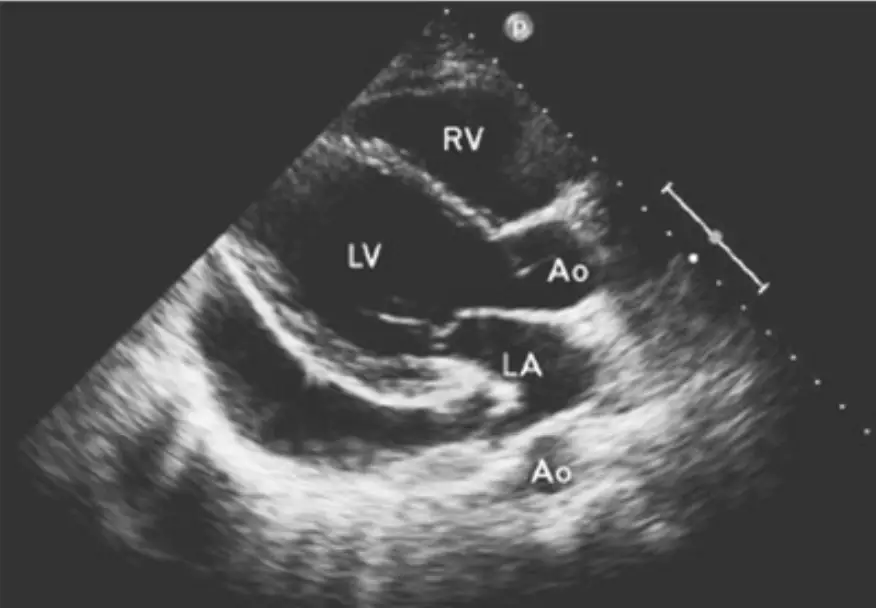

D心臟超音波檢查如圖

心臟超音波(Echo)特徵

- 心包積液:心臟被無回音液體環繞,惡性積液可見纖維素沉積

- RA 收縮期塌陷(RA collapse):最敏感徵象(~80–100%),RA 壁薄壓力最低,最早塌陷

- RV 舒張期塌陷(RV diastolic collapse):高特異